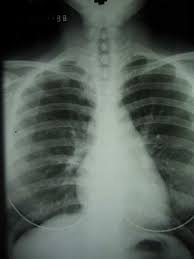

Individuals with pleural mesothelioma may amass some fluid between the lung lining and chest cavity. This can be detected through a chest x-ray, as well as CT scans.

Mesothelioma diagnosis

Diagnosing mesothelioma is often complicated, because the symptoms are similar to those of several other conditions. Diagnosis begins with an assessment of the patient's medical history, as well as any history of asbestos exposure. A physical examination may be performed, including x-rays of the chest or abdomen and lung function tests. A CT (or CAT) scan or an MRI may also be useful. A CT scan is a series of detailed pictures of areas inside the body created by a computer linked to an x-ray machine. In an MRI, a powerful magnet linked to a computer is used to make detailed pictures of areas inside the body. These pictures are viewed on a monitor and can also be printed.